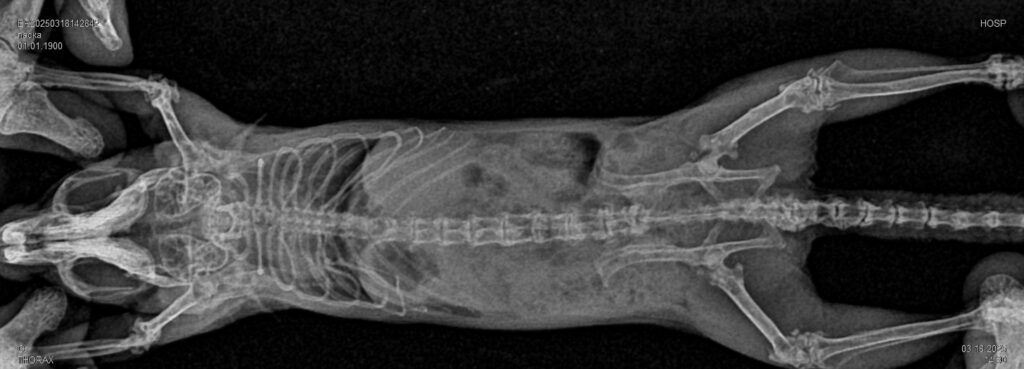

- Для исключения патологий опорно—двигательного аппарата: переломов, дегенеративных изменений костной и хрящевой ткани, дисплазии тазобедренного и локтевого суставов, новообразований костей и ряда других патологий.

- При исследовании позвоночника — с помощью рентгенографии особенно в случае появления у животного неврологических симптомов, хромоты, болей в области спины и двигательных расстройств определяют патологические изменения костной системы и их источники: дегенеративные заболевания позвоночника, такие какие спондилез или артроз; деформации позвоночника.

- Рентген головы, челюстей у домашних животных. Здоровье зубов имеет решающее значение для наших пушистых друзей, и рентген челюстей стал неотъемлемой частью ветеринарной стоматологической помощи. Рентгеновские снимки позволяют ветеринарам оценить проблемы с зубами ниже линии десен, такие как, инфекции корней зубов и переломы, которые не видны во время стандартного осмотра полости рта.

Если животное спокойно, не испытывает сильной боли, стресса и может лежать в необходимом положении, пока ветеринарный врач проводит рентген-диагностику, седация не понадобится. И наоборот, если животное испытывает стресс, беспокойство, боль, ветеринар порекомендует седацию перед проведением рентген-диагностики. Ситуации при которых седация пациента перед рентгенографией будет обязательна: при рентгенографии позвоночного столба, черепа, челюстей, или если мышцы животного должны быть расслаблены для получения максимально чёткого изображения.